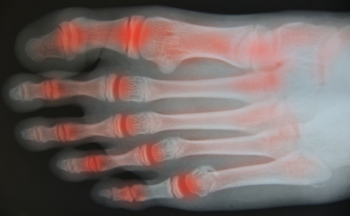

Arthritis is a joint disorder that involves the inflammation of different joints in your body, such as those in your feet. Arthritis is often caused by a degenerative joint disease and causes mild to severe pain in all affected areas. In addition to this, swelling and stiffness in the affected joints can also be a common symptom of arthritis.

Many people suffer from the pain of arthritis, of which there are about 100 varieties. A podiatrist can help you figure out which form of this disease you have through a number of tests. The most common types are osteoarthritis, which is a wearing away of the cartilage between the bones; rheumatoid arthritis, a long-term condition that causes pain, swelling and deformity in the joints; and gout, caused by a buildup of uric acid that results in redness, swelling, and pain affecting the big toe and other joints. Among the ways you can live with arthritis are diet, exercise and pain management. It has been found that eating a Mediterranean style diet (fish, nuts, olive oil, vegetables and fruit) can help reduce the effects of arthritis. It is also suggested that you avoid red meat, poultry and full-fat dairy products, and try to include calcium rich foods to ward off osteoporosis (thinning of the bones). A regular program of exercise is suggested to help keep your weight down and reduce joint stiffness. A number of medications are available to alleviate the pain caused by arthritis. In addition, using heat or ice treatments as needed throughout the day and avoiding activities that increase your pain is suggested. Changing the way you operate with appropriate walking aids, raised toilet seats, and safely navigating in your home can be helpful. If you need more information on how to manage arthritis, please consult with a podiatrist for an examination and treatment options.